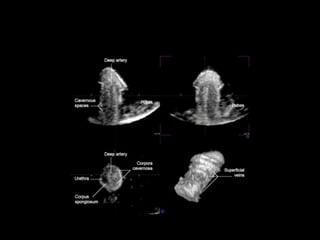

Diagnostico

•    Palpacion de hematoma

•    Incurvarcion

•    Uretrografia retrograda

•    Cavernosografia

•    USG Doppler

•    RMN

Diagnostico • Palpacion de hematoma • Incurvarcion • Uretrografia retrograda • Cavernosografia • USG Doppler • RMN ,Safir M, Mario LA, Service S, Segal MR.American Association for the Surgery of Trauma organ injury severity scale for the kidney. J Trauma 2010;50(2):195-200.